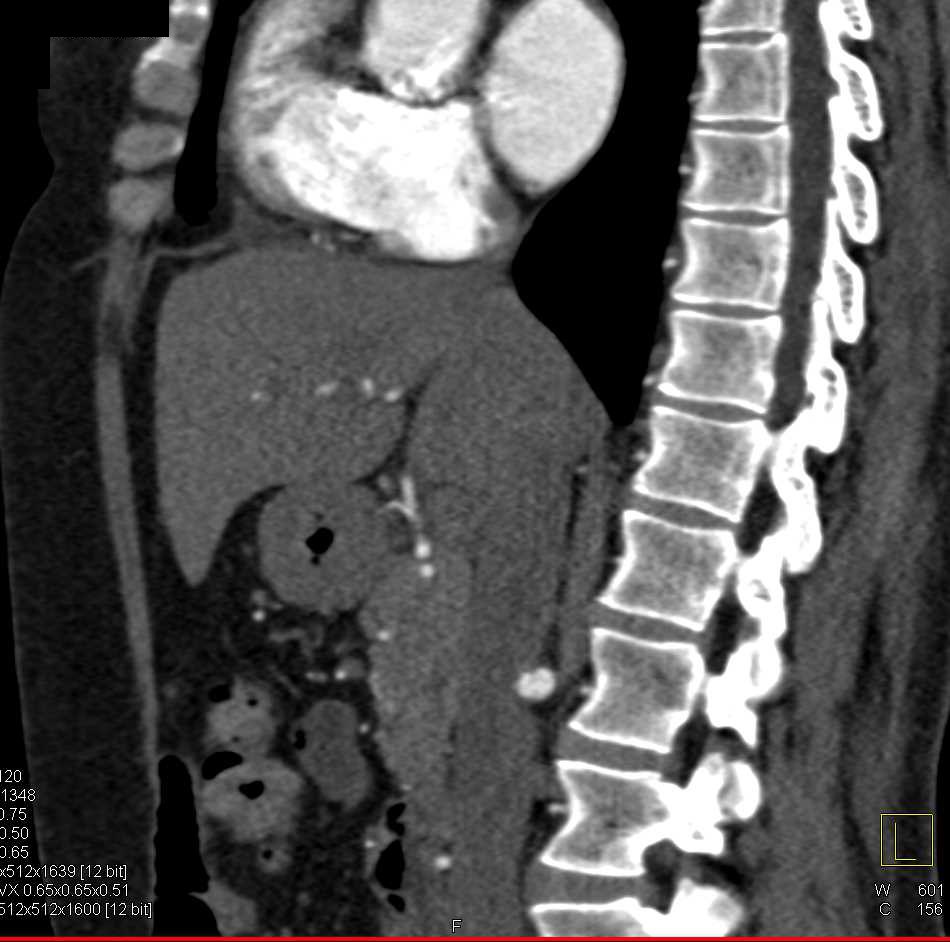

Pseudo lesion Right Renal Fossa